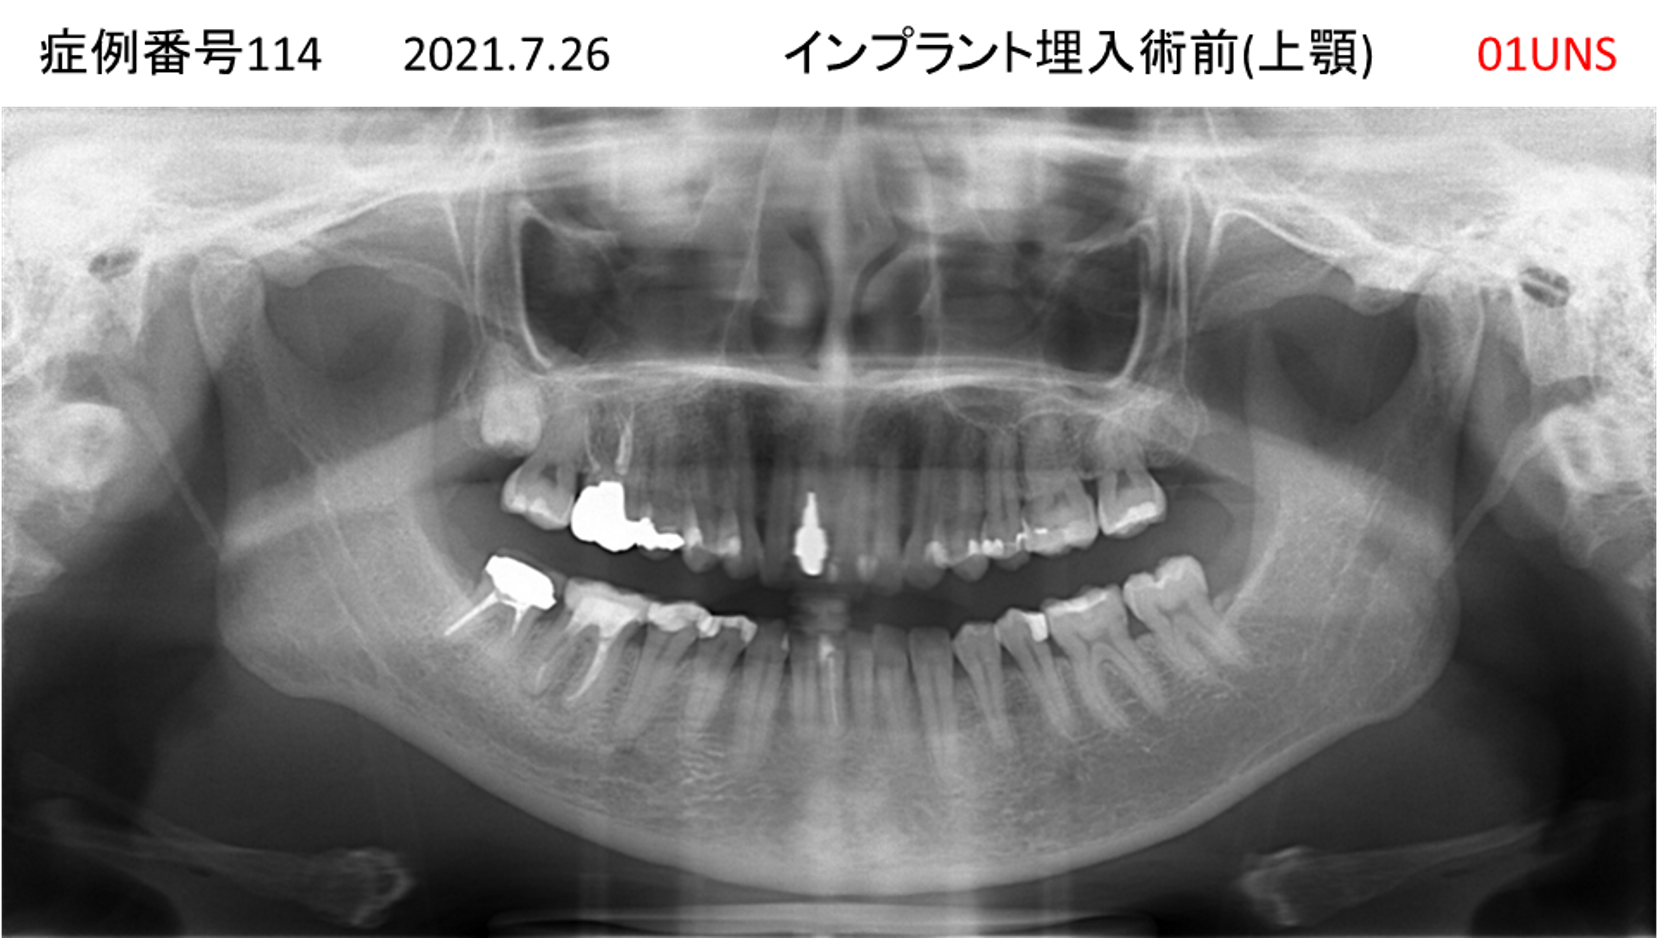

上の前歯が揺れてきてかめない患者様のインプラント症例

| 治療名称 |

インプラント |

| 治療費用 |

335万円+税 |

| 治療期間 |

4か月 |

| 患者さんの症状(主訴) |

上の前歯が揺れてきて噛めない |

| 治療内容 |

サイナスリフト 抜歯即時インプラント |

| 治療結果 |

ちゃんと噛めるようになった。不安がなくなった。見た目がとても良くなったのすごくうれしい。 |

| 治療の注意点(リスク/副作用) |

インプラントが壊れたら再治療が必要 |